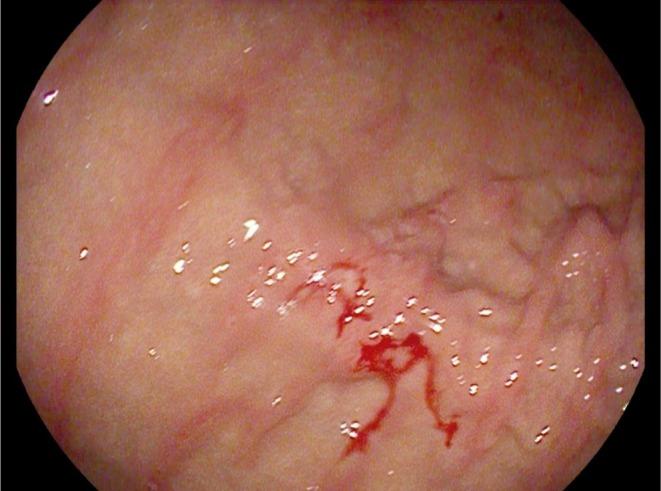

Invasive lobular carcinoma (ILC) of the breast is a rare subtype of breast cancer with distinct metastatic patterns. Although gastrointestinal metastases are rare, they can occur years after initial treatment. This case highlights the diagnostic challenges and management of late-onset gastric metastases. A 68-year-old woman with a history of ILC treated 20 years earlier presented with elevated tumor markers. [F]fluorodeoxyglucose positron emission tomography/computed tomography (FDG PET/CT) revealed hypermetabolic lesions in the stomach and esophagus in this patient with previously diagnosed gastritis and gastroesophageal reflux disease. Endoscopy and biopsies confirmed the presence of metastatic ILC in the stomach. Adjustment of treatment, including exemestane and everolimus, followed by paclitaxel and tamoxifen, resulted in partial disease control. Late-onset gastrointestinal metastases of ILC are uncommon and require special vigilance, particularly in patients with associated benign gastrointestinal pathologies, which may delay diagnosis. Persistent or new-onset gastrointestinal symptoms in breast cancer patients warrant thorough evaluation, including FDG PET/CT imaging and histological confirmation.

乳腺浸润性小叶癌(ILC)是一种罕见的乳腺癌亚型,具有独特的转移模式。尽管胃肠道转移很少见,但可在初始治疗数年之后发生。本病例突出了晚期胃转移的诊断挑战及处理方法。一名20年前曾接受过ILC治疗的68岁女性,出现肿瘤标志物升高。[F]氟脱氧葡萄糖正电子发射断层扫描/计算机断层扫描(FDG PET/CT)显示,该先前诊断为胃炎和胃食管反流病的患者,胃和食管出现代谢增高性病变。内镜检查及活检证实胃内存在转移性ILC。调整治疗方案,包括使用依西美坦和依维莫司,随后使用紫杉醇和他莫昔芬,实现了部分疾病控制。ILC的晚期胃肠道转移并不常见,需要特别警惕,尤其是对于伴有胃肠道良性病变的患者,这可能会延迟诊断。乳腺癌患者持续存在或新出现的胃肠道症状需要进行全面评估,包括FDG PET/CT成像及组织学确诊。